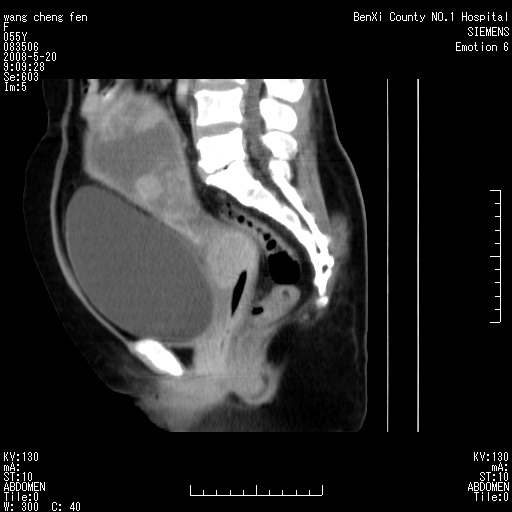

左侧附件区巨大囊实性病灶,边缘光整,病灶囊壁较厚,增强示囊壁及实性部分明显强化,强化呈度与宫体实质大致相同,宫腔积液征像,未见盆腔积液等其他异常,考虑左侧卵巢囊腺癌,不除外囊腺瘤及浆膜下肌瘤坏死

左侧附件区巨大囊实性病灶,边缘光整,病灶囊壁较厚,增强示囊壁及实性部分明显强化,强化呈度与宫体实质大致相同,宫腔积液征像,未见盆腔积液等其他异常。绝经后阴道流血3个月,结合病史左侧卵巢囊腺癌首先考虑,宫腔扩大不除外累及。期待结果。

支持浆膜下子宫肌瘤.之前由于网络原因未看全图片,现在重看,宫颈见一类圆形低密度影,增强轻度强化,低于肌层强化,宫腔扩大,考虑宫颈癌伴宫腔积液可能性大.

囊实性肿块分隔厚度较大,厚薄不均,增强实性成分明显强化,有不规则阴道流血,卵巢囊腺癌可能性大。

1,宫颈部占位,宫颈癌?2,左侧附件区囊实性占位,界较清,实质部分强化明显。考虑浆膜下或阔韧带肌瘤囊变可能大。囊腺类肿瘤不除外。